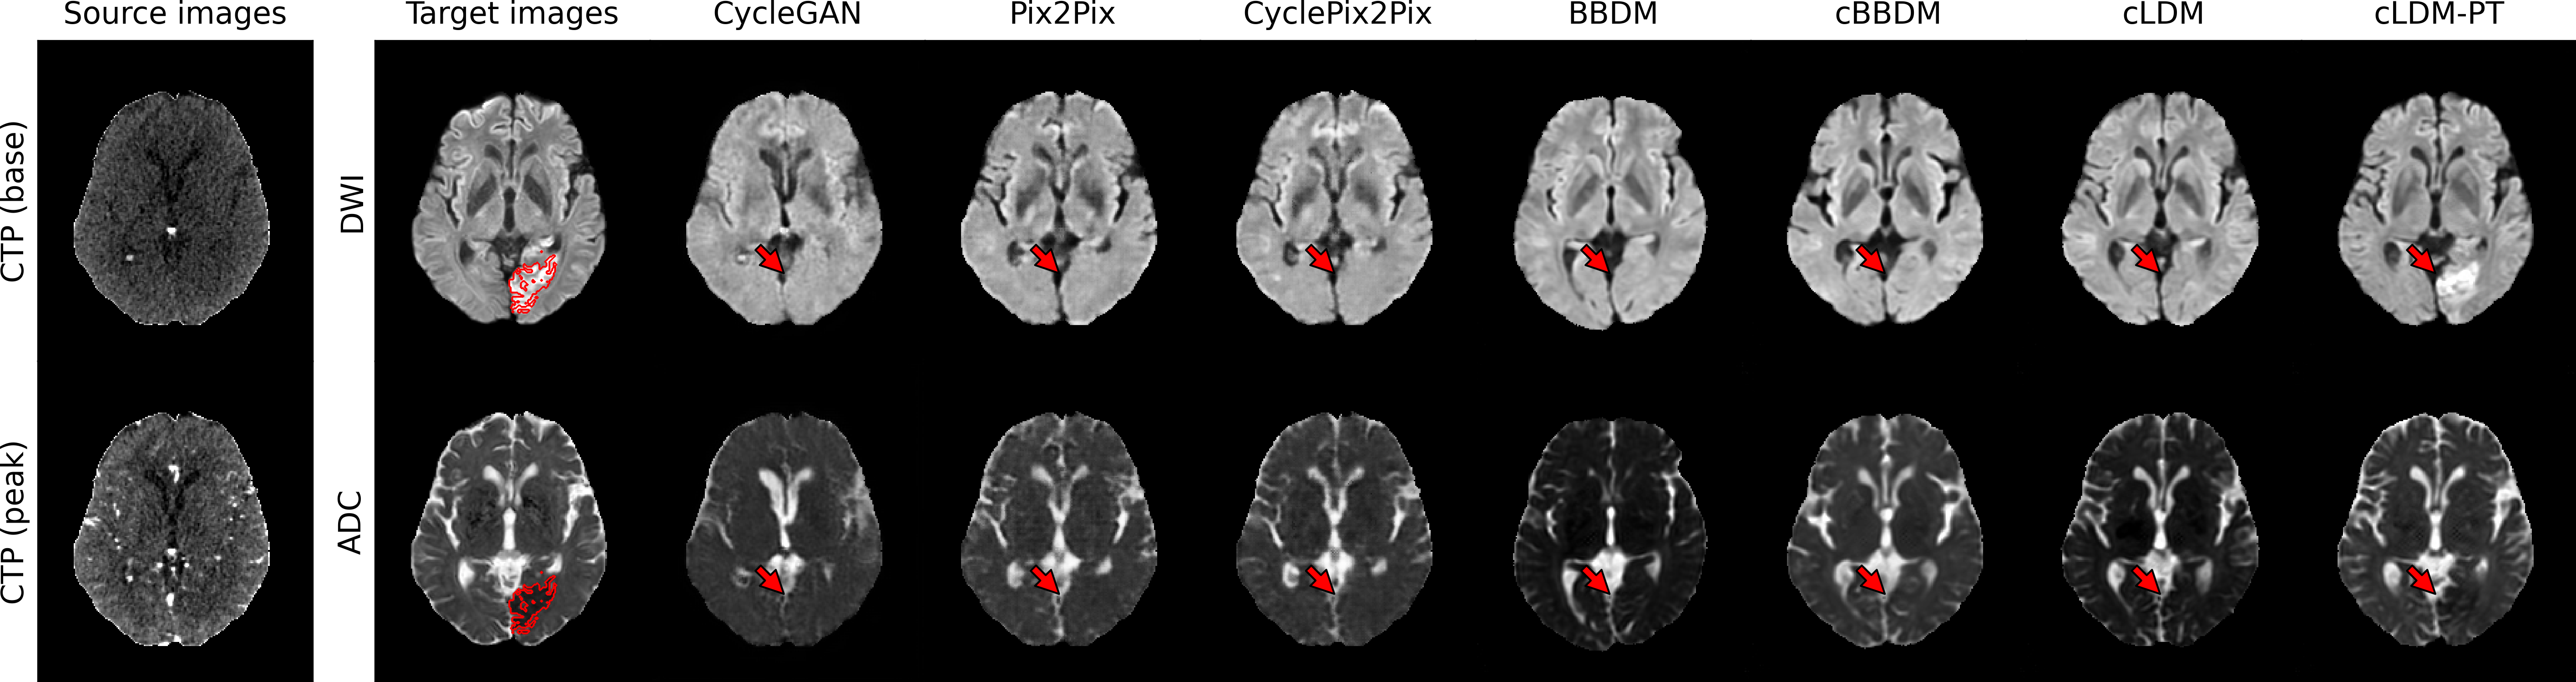

3.2.2 Qualitative Evaluation

Figure 3 visualizes synthesized DWI and ADC from CTP of acute ischemic stroke patients with lesions in various brain regions. Due to low signal-to-noise ratio of CTP, it is difficult to accurately estimate ischemic core volumes. Small infarcts such as lacunar infarcts are also poorly visualized in CTP. These factors make it challenging for generative models to accurately reconstruct ischemic lesions in synthesized MRI. While the diffusion model series generates more realistic images compared to GAN-based models, they encounter difficulty in lesion delineation. Our model, cLDM-PT, excels in lesion delineation and demonstrates exceptional ability to generate accurate and detailed images.